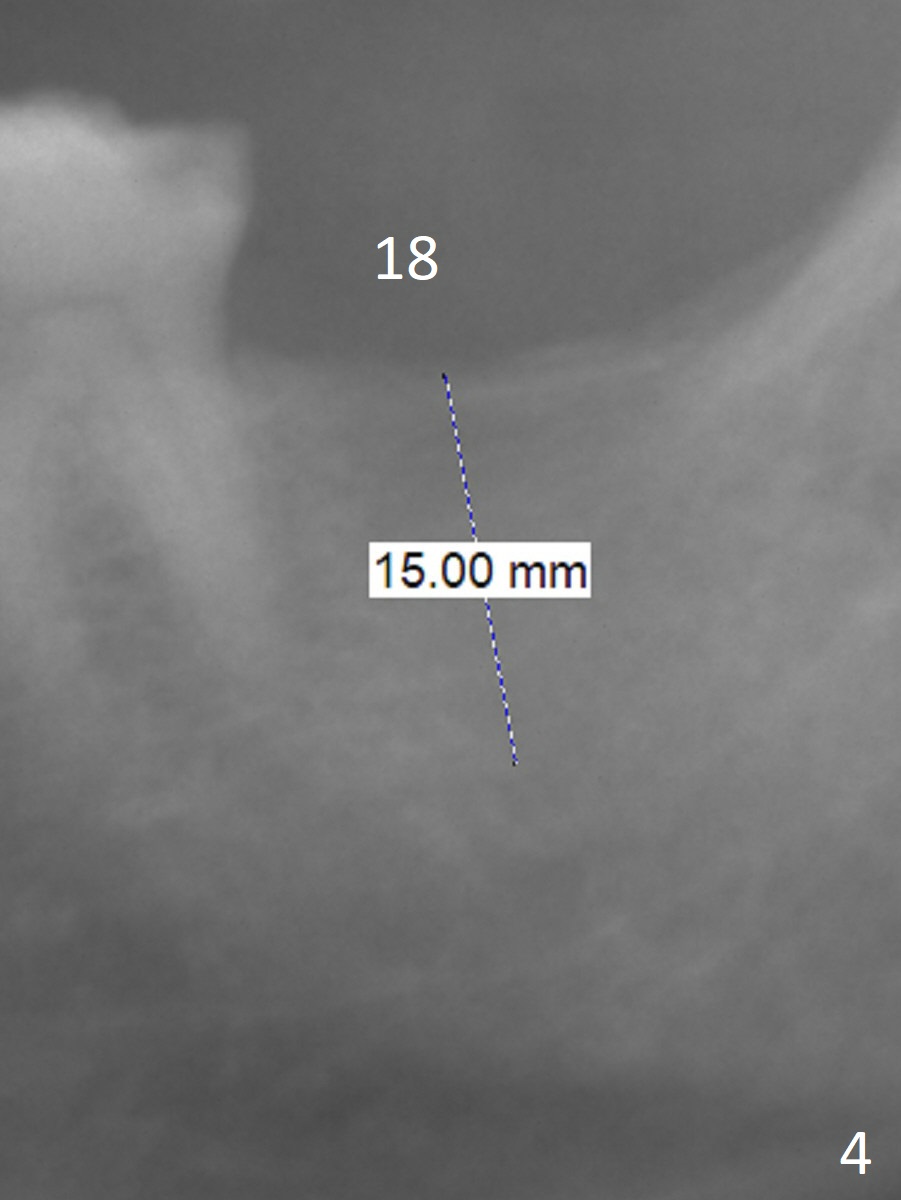

A 58-year-old man has history of temporomandibular joint disorder as related to severe occlusal breakdown and missing tooth #18 (Fig.1,4). The tooth #29 is also missing; the tooth #30 has shifted and tilted mesial. Severe pain develops at #30 two years after MOL composite (Fig.3). The patient insists on extraction and implant, although pulpotomy has been done to alleviate the pain. Although there is sufficient bone height, IS implants will be used because of primary stability and apparent better implant/abutment binding as compared to IBS (with tendency of screw loosening). Osteotomy will be initiated in the mesial socket at #30. Measure the whole length of drills. Find 17-8 mm mark, which will be used as soft tissue landmark.

Since the bone density at #30 is low, underprepare the site #18. The depth will be 15 mm with flapless technique. Prepare Magic Split and Expanders.